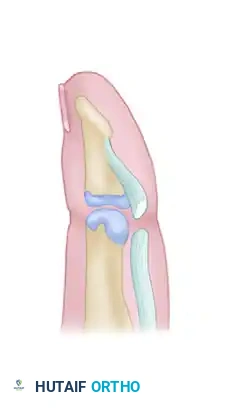

Figure 2: Placement of a locking core suture through the proximal stump of the flexor digitorum profundus tendon.